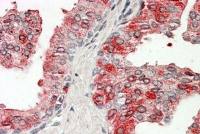

IHC-P analysis of formalin fixed human lung cancer tissue section using GTX54920 Aggrecan antibody.

Antigen retrieval : Heat mediated antigen retrieval with sodium citrate buffer (pH 6.0)